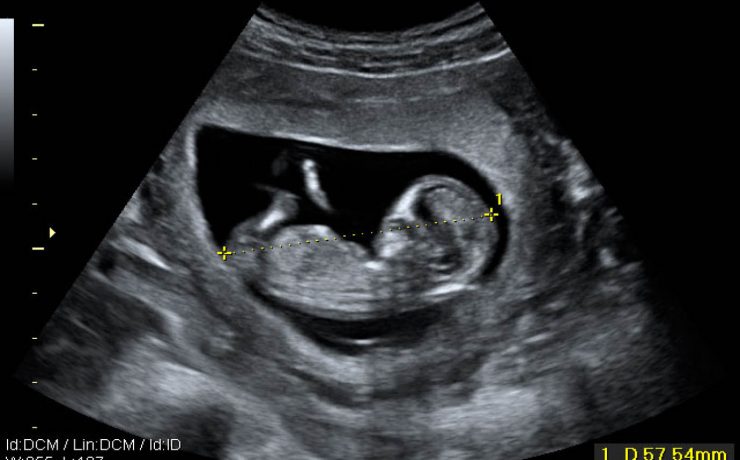

Las vías biliares intrahepática transcurren adyacentes a las raíces de la vena porta y las ramas de la arteria hepática. Los conductos hepáticos derecho e izquierdo se unen para formar el conducto hepático común a nivel del hilio hepático, el cual mide aproximadamente 30mm de longitud y se une al